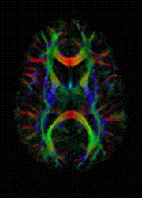

Tractographic reconstruction of neural connections via DTI

The imaging of this property is an extension of diffusion MRI. If a series of diffusion gradients (i.e. magnetic field variations in the MRI magnet) are applied that can determine at least 3 directional vectors (use of 6 different gradients is the minimum and additional gradients improve the accuracy for "off-diagonal" information), it is possible to calculate, for each voxel, a tensor (i.e. a symmetric positive definite 3×3 matrix) that describes the 3-dimensional shape of diffusion. The fiber direction is indicated by the tensor's main eigenvector. This vector can be color-coded, yielding a cartography of the tracts' position and direction (red for left-right, blue for superior-inferior, and green for anterior-posterior). The brightness is weighted by the fractional anisotropy which is a scalar measure of the degree of anisotropy in a given voxel. Mean diffusivity (MD) or trace is a scalar measure of the total diffusion within a voxel. These measures are commonly used clinically to localize white matter lesions that do not show up on other forms of clinical MRI.[58]